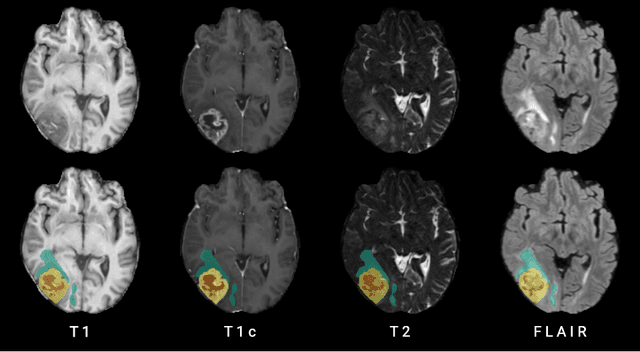

Abstract:Human ratings are abstract representations of segmentation quality. To approximate human quality ratings on scarce expert data, we train surrogate quality estimation models. We evaluate on a complex multi-class segmentation problem, specifically glioma segmentation following the BraTS annotation protocol. The training data features quality ratings from 15 expert neuroradiologists on a scale ranging from 1 to 6 stars for various computer-generated and manual 3D annotations. Even though the networks operate on 2D images and with scarce training data, we can approximate segmentation quality within a margin of error comparable to human intra-rater reliability. Segmentation quality prediction has broad applications. While an understanding of segmentation quality is imperative for successful clinical translation of automatic segmentation quality algorithms, it can play an essential role in training new segmentation models. Due to the split-second inference times, it can be directly applied within a loss function or as a fully-automatic dataset curation mechanism in a federated learning setting.